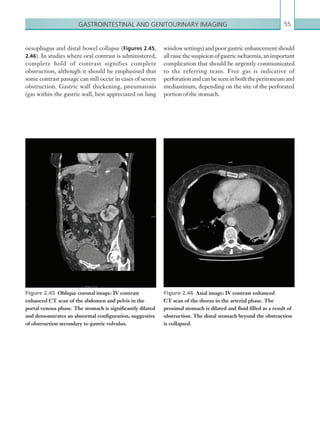

• 35.

13Thoracic imaging should neverdelay urgent thrombolysis if massive pulmonary embolism is suspected clinically. (See Table 1.6.) Radiological findings Computed tomography pulmonary angiogram Interpretation of CTPA studies should begin with an assessment of the quality of the study, namely the degree of pulmonary artery contrast opacification and any potential breathing artefact. An average attenuation of at least 250 Hu is required in the main pulmonary trunk to accurately diagnose more distal emboli. Opacification depends on the size and site of IV access, rate of injection and exact scan protocol; inspiration just prior to scanning can cause poorly MODALITY PROTOCOL CT Pulmonary angiogram: 100 ml IV contrast via 18G cannula, 4 ml/sec. Bolus track centred on main pulmonary artery. Scan from thoracic inlet to diaphragm level. Table 1.6 Pulmonary embolus. Imaging protocol. opacified blood to be introduced into the pulmonary arterial system, resulting in the mixing and dilution of contrast. The precise sensitivity of CTPA studies varies according to both the quality of contrast opacification and the degree of artefact (e.g. breathing). It may be the case that contrast opacification centrally is adequate; however, emboli more distal in the pulmonary arterial system cannot be excluded. It is good practice to quantify to what arterial level emboli can be excluded: lobar, segmental or subsegmental. Thepulmonaryarterialsystemshouldbescrutinised systematically using multiplanar reformatting. A rounded intraluminal filling defect within a pulmonary artery, which may also cause slight vessel expansion, is consistentwithanacuteembolus(Figure 1.11).Itcanbe difficult to appreciate emboli if the pulmonary arteries are inspected on standard soft tissue window settings, since they can be obscured by the dense IV contrast. Inspection on a relatively wide window setting (width 700, level 100) can alleviate this. A gradual decrease in opacification of the distal segmental and sub- segmental pulmonary arteries on a suboptimal study should not be confused with multiple emboli. Poorly opacified pulmonary veins can also be misinterpreted as emboli within the arterial system. Findings seen in association with pulmonary embolism include Figure 1.11  Axial image: IV contrast enhanced CT pulmonary angiogram. A filling defect is outlined by intravenous contrast in the right main pulmonary artery consistent with acute embolus (arrow). K22247_C001.indd 13 16/05/15 3:06 AM

• 36.

Chapter 114 narrowing dueto recanalisation (Figures 1.14). A focal linear intraluminal filling defect within a pulmonary artery is suggestive of an arterial web, which can be seen as a result of chronic emboli. Secondary pulmonary artery hypertension can result from multiple chronic emboli. The main sign of pulmonary hypertension on CT is enlargement of the main pulmonary artery (greater than 34 mm or larger than the corresponding ascendingaorta;Figure 1.15).Mosaicattenuationofthe lung parenchyma can also be seen in cases of chronic pulmonary emboli, although this appearance has a wide differential diagnosis (Figure 1.16). pleural effusions, atelectasis and pulmonary infarcts. The latter present as peripheral wedge-shaped areas of consolidation,which inthesubacutephasemaycavitate (Figures 1.12a–c, 1.13). Chronic pulmonary embolism can provide a diagnosticchallengefortheradiologist,althoughseveral findings can be observed that imply this diagnosis. Calcification of a filling defect suggests chronicity. Otherradiologicalsignsincludefillingdefectsthatcause narrowing (as opposed to expansion), eccentric filling defects that form an obtuse (as opposed to acute) angle with the pulmonary artery wall and an abrupt artery Figures 1.12a–c  Axial images: IV contrast enhanced CT scans of the thorax in the arterial phase. Peripheral, wedge-shaped area of consolidation shown. Over time, the area of consolidation develops an irregular, thick rind with areas of cavitation centrally due to infarction. Note the associated pulmonary arterial filling defects in 1.12b and 1.12c consistent with pulmonary emboli. (a) (b)(b) (c) K22247_C001.indd 14 16/05/15 3:06 AM